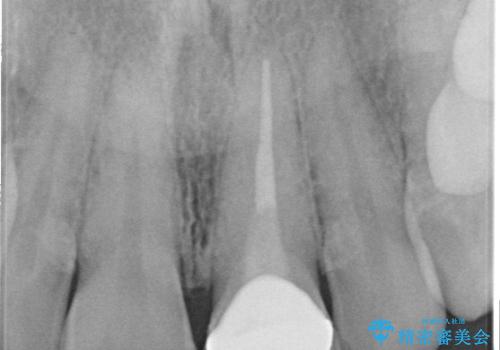

- 前歯をメタルの被せものにしており、セラミックに変えるのを希望された患者様です。

土台も金属だったため、歯がかなり黒く変色していました。

色は完全にとるのが不可能であることをご了承頂いた上で、土台と被せものの治療を行いました。

今回は歯自体が黒くなって歯茎から透けて見えている黒ずみのため、セラミック治療で改善させることは困難だというお話をしました。その上でできる範囲できれいに治療することになりました。

今回のように歯自体が金属イオンで黒く変色すると、被せものをメタルフリーにしても黒ずみをすべて隠すのは困難になります。一方、被せものの金属が見えていることが原因の黒ずみの場合は、セラミック治療できれいになりますので、気になる方は一度ご来院ください。